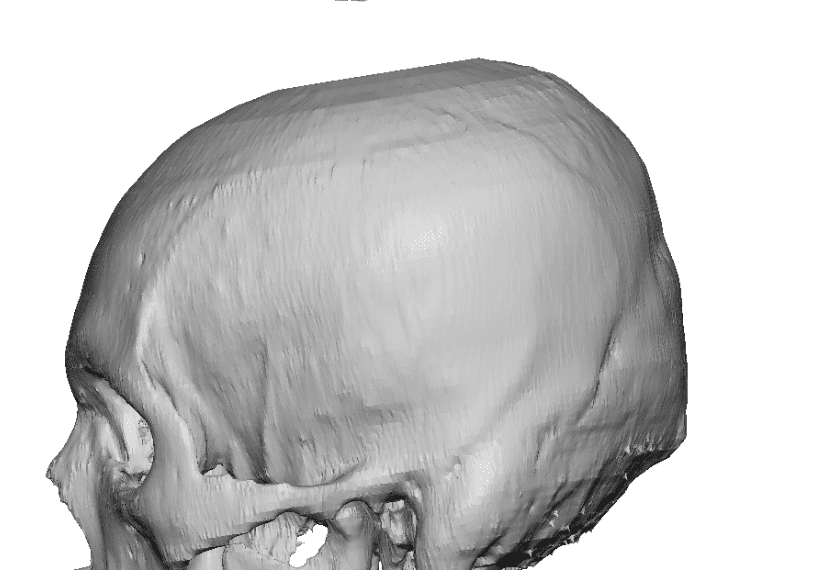

Desire for an improved head shape so that it looks rounder and not so peaked or sloped.

Placement of custom skull implant for parasagittal augmentation to create a rounder head shape. An example of what appears to be a high sagittal crest that is really low parasagittal skull areas.

Desire for an improved head shape so that it looks rounder and not so peaked or sloped.

Placement of custom skull implant for parasagittal augmentation to create a rounder head shape. An example of what appears to be a high sagittal crest that is really low parasagittal skull areas.